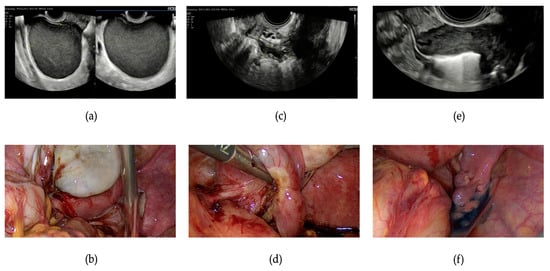

The data, albeit preliminary, on the concordance between uEFI and sEFI clearly indicate a high agreement (k = 0.7) between the preoperative assessment and laparoscopic evaluation, suggesting, in line with the latest ESHRE guidelines, that laparoscopy should be avoided solely for diagnostic purposes [6]. It is essential to emphasize the crucial role of specialized sonographers in the diagnosis and evaluation of endometriotic pathology, especially in cases with deep infiltrating endometriosis [15] (as seen in Figure 3), supporting the centralization of patients with endometriosis seeking pregnancy in specialized centers, as practiced in our center (following the terms and definitions of the IDEA-group [13]). This represents an initial limitation to the widespread adoption of preoperative EFI across all facilities, as also highlighted in the previous article on this topic by Tomassetti et al. [12]. Similar to the aforementioned article, we report a nearly identical predictive capacity for fertility outcomes between preoperative and surgical analyses.

Figure 3. Presurgical and intraoperative images of a patient who underwent laparoscopy for ovarian and deep infiltrating endometriosis, illustrating the agreement between the ultrasound and surgical findings. (a) An ultrasound image depicting a typical endometrioma of the left ovary with a characteristic ground glass appearance; (b) a laparoscopic view of the left ovarian endometrioma; (c) an endometriotic nodule of the left parametrium, causing stretching of the ipsilateral tube and adhesions between the ovary, tube, and bowel; (d) an intraoperative view of the left tube, which is dilated, convoluted, and adhered to the ovary and peritoneal nodule. Subsequent chromopertubation will confirm the lack of patency of the left tube. (e) Hysterosalpingo-foam sonography (HyFoSy) of the right tube demonstrating the patent status on a presurgical examination. (f) Chromopertubation with methylene blue confirming the patency of the right tube during surgery.